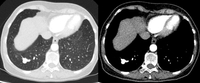

Tomografia computadorizada (TC) mostrando nódulo alongado periférico no lobo superior esquerdo, com captação de contraste e lado de alimentação e drenagem nítido, condizente com pequena malformação arteriovenosa

Do acervo de Dr. George Tsaknis, MD, PhD, FRCP (Londres), MRQA, MAcadMEd, PGCert; usado com permissão